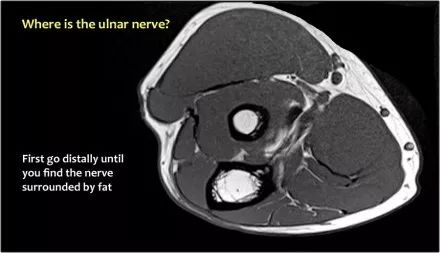

因此,当我们回到图像时,您会发现很难找到神经。任何这些皮下结构都可以是转位神经。一种方法是远端跟随结构,直到你发现远端的尺神经位于由脂肪包围的前臂近端的正常位置。然后当你向近端跟随它时,你会发现这是皮下移位。

在这种情况下,有神经炎。神经增大。在T2W图像上有高信号。另一个标志是在矢状图像(箭头)上看到的束的不均匀扩大。